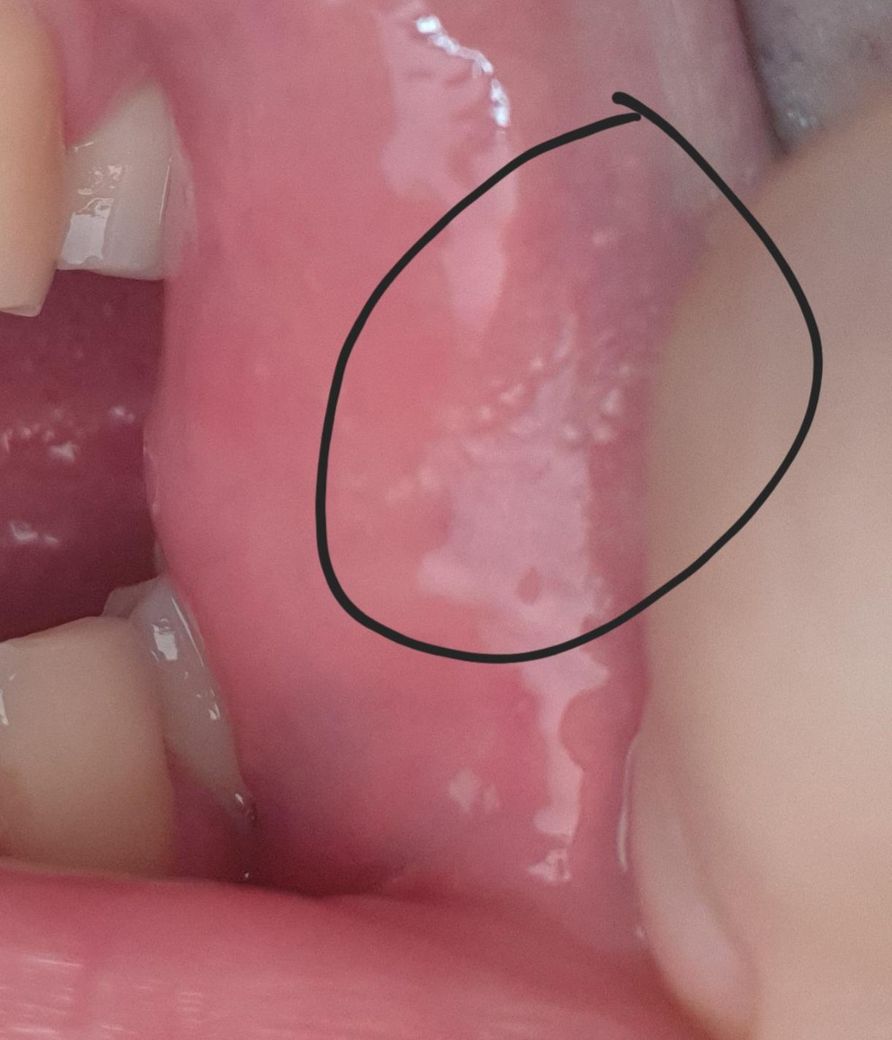

3주전에 입안, 입술에 포다이스반을 발견하고 처음에 헤르페스 첫발병인지알고 발트랙스정을 복용했으며 통증없고 수포형태가아니라서 헤르페스는 아닌걸로보입니다

오늘 세수 후 인중수염에서 하얗게 뭔가 생기길래 털을 뽑아서보니 입주변 모든모공에서 하얗게 피지가 올라온걸 확인했습니다 클렌징오일이나 세수, 압출시도해도 안나오더라구요

설명한 양상만 보면 질환보다는 피지선 활동 증가로 인한 피지 축적(sebaceous filament) 가능성이 가장 흔합니다. 인중과 수염 부위는 피지선이 매우 많은 부위라 세안 직후 모공 안의 피지가 하얗게 도드라져 보일 수 있습니다. 이는 여드름이나 감염이 아니라 정상적인 피지 배출 구조가 보이는 현상으로, 대부분 특별한 치료가 필요한 질환은 아닙니다.

입술에서 관찰한 '포다이스 반(Fordyce spots)'과 같은 피지선 노출 현상도 입 주변 피부에 함께 보일 수 있습니다. 포다이스 반은 피지선이 표면 가까이 위치해 작은 흰색 또는 노란 점처럼 보이는 정상 변이이며 통증이나 수포가 없는 경우가 일반적입니다. 반면 헤르페스는 보통 통증을 동반한 작은 수포가 군집 형태로 생긴 뒤 미란이나 딱지로 진행하므로, 설명한 모공마다 하얀 피지가 보이는 양상과는 임상적으로 다릅니다.